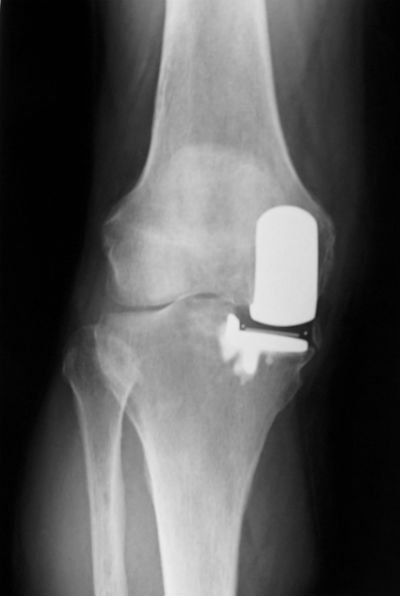

As things progress patients often develop severe night pain and when you are getting to that stage most people want to get something done about it. If lifestyle modification hasn’t worked, you have tried the anti-inflammatories, you have tried to lose weight, you’ve stopped doing impact exercises, you’ve tried your glucosamine, you’ve even gone to the trouble of buying an offloader brace and tried to offload the painful knee compartment (and they don’t tend to work very well with the braces – some people get on with them but most people struggle), then the next step for you is going to be surgery. The surgery for purely varus or valgus osteoarthritis is either an osteotomy (left image) or a knee replacement (partial knee replacement or a complete knee replacement) (right image).